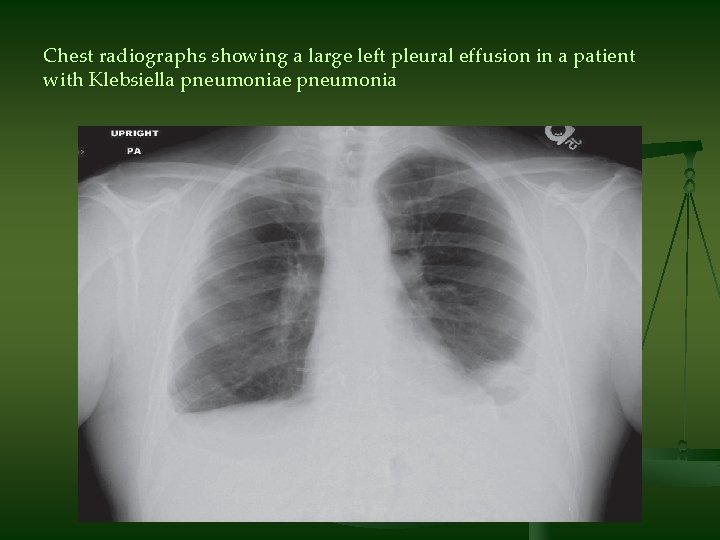

Chest radiographs showing a large left pleural effusion in a patient with Klebsiella pneumoniae pneumonia